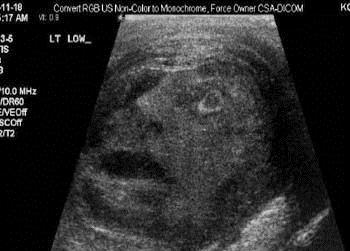

Man's 'Screaming Face' Appears In Ultrasound

An ultrasound of a tumor sent two top docs into a state of disbelief, and not because of their medical training.

Staring back at them on the ultrasound screen appeared to be the face of a man screaming!

The 2009 image was recently discovered by Drs. Naj Touma and Gregory Roberts who were doing research at Toronto's Queen's University Medical School, and scrolling through hundreds of tumor ultrasounds.

“It was very ghoulish, like a man screaming in pain. His mouth was open and it looked like one eye was gouged out,” Touma told The Toronto Star.

The good news for the unidentified patient was that the tumor turned out to be benign, and had been caused by an infection.

The bad news -- it was a testicular tumor and the patient had to have his [expletive] removed.